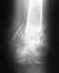

Безусловно, перелом позвонка срастется без лечения. Проблемой является нарушение его формы, что приводит к изменению формы позвоночника. Отсутствие боли через месяц после травмы - это хорошо, но ни о чем судить не позволяет.